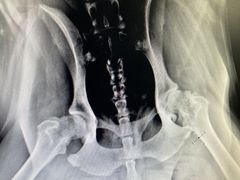

• 小叮当动物医院·骨科·眼科

• -小叮当动物医院·骨科·眼科

匿名用户 | 22-04-08